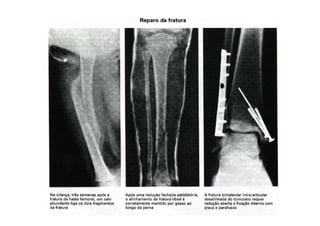

REPARO E CICATRIZAÇÃO

• Final do reparo e da cicatrização óssea 6

meses após o trauma